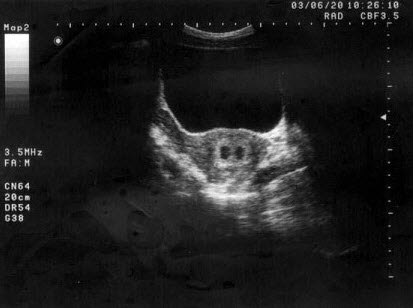

根据以下肝超声检查声像图,诊断为()

A.肝癌并门脉癌栓

B.肝硬化

C.脂肪肝

D.肝炎

E.血吸虫性肝硬化并门脉血栓